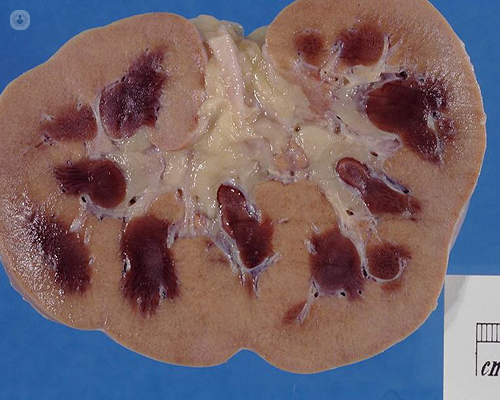

- Enfermedades con síntomas semejantes: formación y migración de coágulos en la vía urinaria causada por una lesión tumoral o inflamatoria de la vía urinaria o asociada con trastornos de la hemostasia y la eliminación de fragmentos de parénquima renal necrótico, que puede observarse en la necrosis papilar por analgésicos y en la papilitis necrosante en pacientes diabéticos. Se rescatan los antecedentes y observar en el sedimento urinario en fresco de los fragmentos papilares mencionados.

La papilitis necrotizante es una complicación de diversas patologías que tienen en común el desarrollo de algún grado de isquemia renal, las más importantes son la Diabetes Mellitus, la nefropatía por antiinflamatorios no esteroideos y la infección urinaria, estando esta última condición presente en más de 2/3 de los casos. Su espectro clínico es muy amplio, desde casos asintomáticos hasta casos de insuficiencia renal aguda obstructiva y muerte, de no mediar tratamiento oportuno.